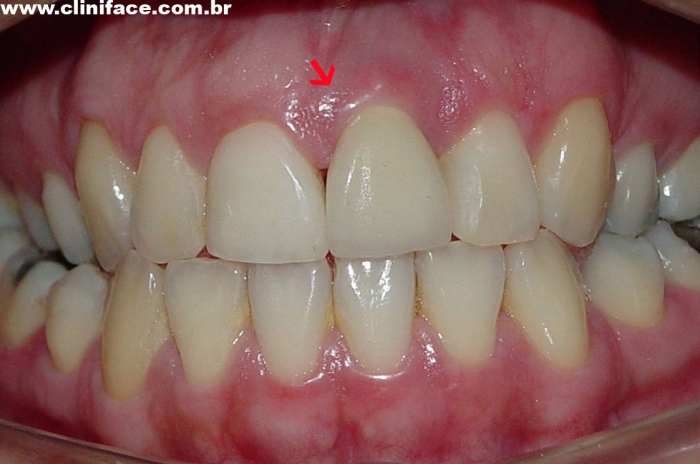

Sorriso inicial

Dente 21 com fratura